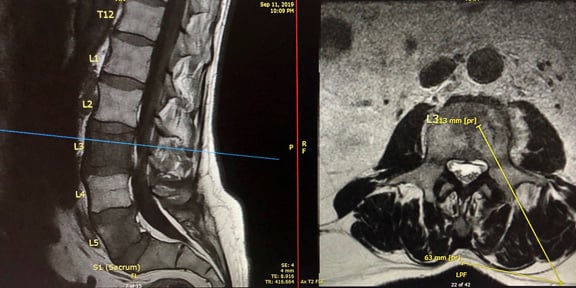

Dr. Massari, a member of the UMass Neurointerventional Radiology Group performed a transpedicular lumbar vertebra biopsy on a patient referred by a local practitioner. Pictured is the radiology team from left to right: Lisa Laprade, procedural technician, Jayne Roose, RN, Kalyn Dhroso, PA, Francesco Massari MD, Amin Chaoui, MD, Danielle McHugh RT CT.